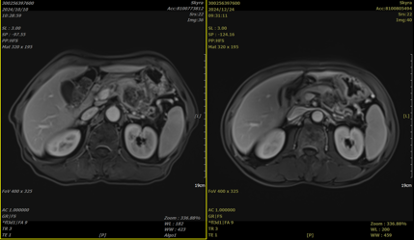

2.病史:患者于2024年4月无明显诱因出现上腹部疼痛。当时未予重视,未行治疗。后患者自觉疼痛逐渐加重,呈持续性,伴背部疼痛,遂于2024-09-28就诊于当地医院,行腹部MRI提示:胰腺体尾部可见一不规则稍长T1稍长T2及长T1长T2混杂信号肿块,DWI呈高信号,边界欠清,周围脂肪层模糊,与相邻胃壁关系密切,范围大小约5.6cm*3.4cm*2.8cm。累及脾动静脉,致胰源性门脉高压症;少量腹水;肝内多发异常强化灶;胰腺周围、腹膜后多发小淋巴结,部分转移不除外。PET-CT提示:胰腺体尾部可见不规则软组织密度肿块,FDG摄取异常增高,SUVmax6.1,大小约5.6cm*3.7cm*3.8cm,病变边界不清,向前与相邻胃壁分界不清,向后与相邻脾动静脉分界不清。胰腺病变周围、肝胃间隙及腹膜后可见多发淋巴结,FDG摄取增高,SUVmax2.0,大者短径约0.7cm。肝实质可见多发结节状FDG摄取增高灶,同机CT部分见稍低密度结节,左外上段为著,SUVmax3.5,大者直径约1.2cm。于2024-10-08就诊于我院,入院后完善相关检查,胰腺体尾部病灶穿刺活检提示:(胰体占位穿刺组织条)胰腺导管腺癌,中分化;免疫组化结果显示:C-erbB-2(0),CK19(+),CK20(-),CK7(+),Ki-67(阳性率≈30%),P53(错义突变),S100p(弱+)。MLH1(+),MSH2(+),MSH6(+),PMS2(+)。基因检测提示:KRAS G12V突变。明确诊断后予以胰腺癌及肝转移癌碳离子放疗,总剂量:PTV1 40Gy(RBE)/10Fx,PTV2 8Gy(RBE)/2Fx,PTV3 8Gy(RBE)/2Fx,PTV4 44Gy(RBE)/11Fx,PTV5 16Gy(RBE)/4Fx。同步于2024-10-12起予以“白蛋白紫杉醇+吉西他滨”全身静脉化疗。2024-11-12复查腹部MRI提示胰腺Ca治疗后复查,胰腺体尾部囊实性占位,与相邻胃壁、脾动静脉分界不清,较前(2024-10-10)病灶范围缩小,肝内数个异常强化结节,多考虑转移,较前部分缩小,腹腔内及腹膜后多发淋巴结,较前部分缩小。

4.治疗效果

治疗前 治疗后